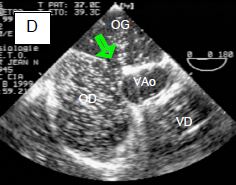

Le débit du shunt G-D est fonction de la taille de la CIA et de la compliance respective des cavités droites et gauches: lorsque celle du VG baisse, la POG s'élève et le shunt G-D augmente, parce que le flux du shunt est majoritairement diastolique. Il conduit à une surcharge de volume à droite, donc à une dilatation de l'OD, du VD et de l'AP (Figure 14.37).

Figure 14.37 : Communication interauriculaire. Schéma de la silhouette des 4 chambres cardiaques en cas de CIA avec un shunt gauche → droit important (flèche). L'OD et le VD sont dilatés; le VD est hypertrophié. L’apex du cœur est formé par le VD, non par le VG. La dilatation du VD entraîne secondairement une insuffisance tricuspidienne.

Le VD est dilaté et hypertrophié pour accommoder la surcharge de volume (Vidéo).